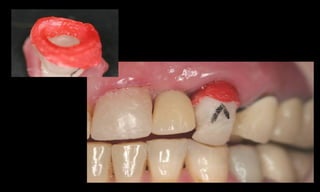

Resultados estéticos periimplantares otimizados

(Abboud, M. IJOMI, 2005).